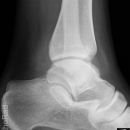

Sprunggelenk

Weber A

Es wurden keine Bilder gefunden.

Weber B

Weber C + dorsales Volkmann

Trimalleoläre

Vorderes Volkmann + lat. Talusschulter